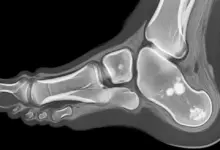

- Radiografias: incluem incidências com estresse para flagrar subluxação.

- Ressonância magnética: mostra integridade ligamentar e lesões associadas.

- Tomografia: apoio em deformidades ósseas e planejamento cirúrgico.